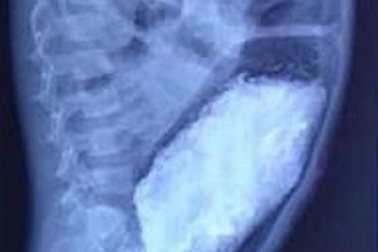

Bị táo bón kéo dài, 3kg phân đóng trong ruột bé trai 5 tuổiBị táo bón từ khi chào đời, ruột cháu bé 5 tuổi phình giãn hơn 20cm, đóng gần gần 3kg phân. Đây là bệnh phình đại tràng bẩm sinh do nguyên nhân vô hạch chiếm vị trí hàng đầu trong hội chứng tắc ruột ở trẻ sơ sinh.